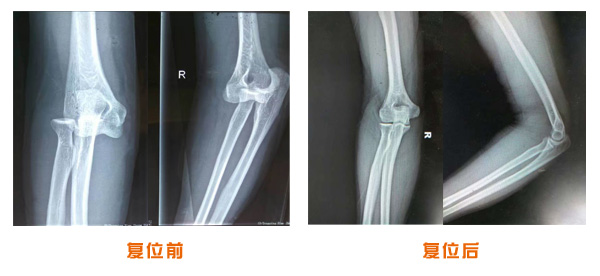

肘關(guān)節(jié)脫位骨折治療前后對比